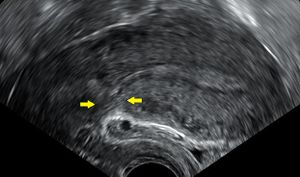

فريق طبي يجري عملية ولادة قيصرية.[1]  | |